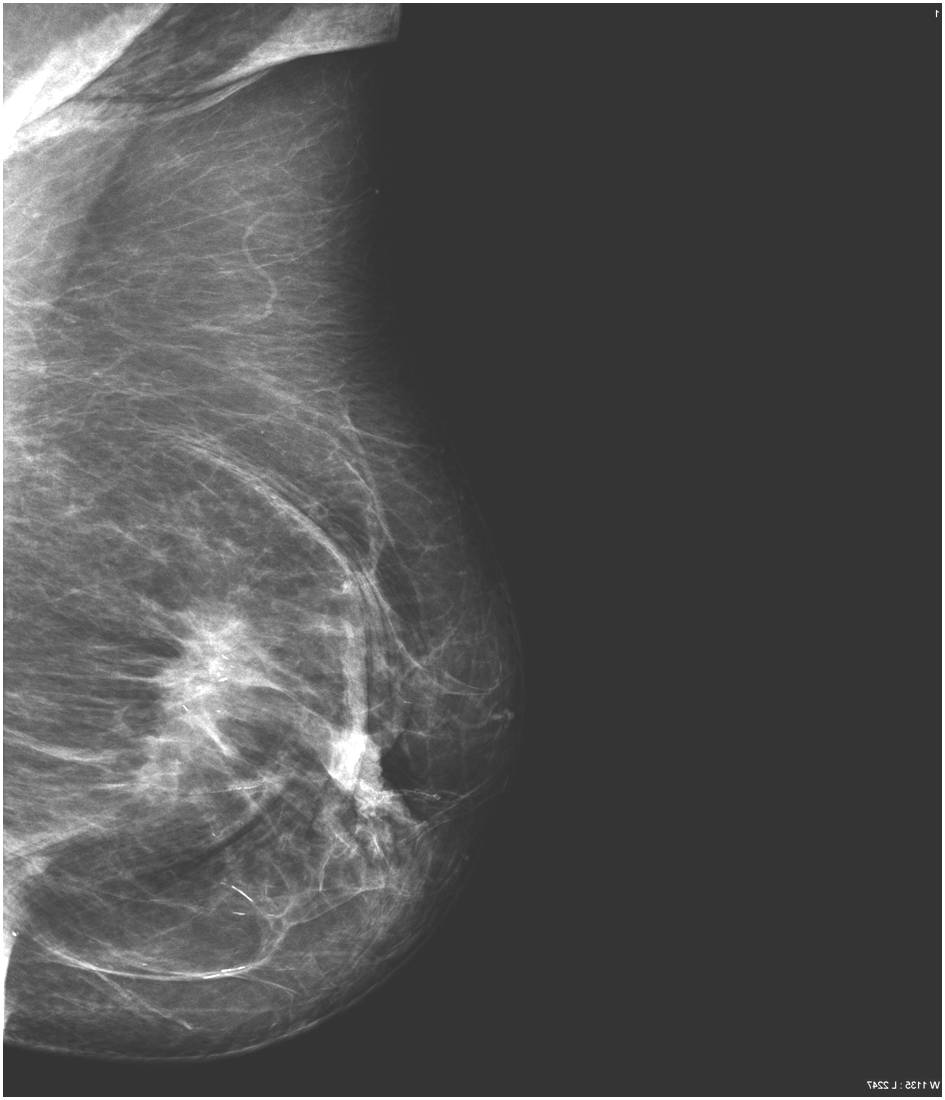

Ill-defined margins, with uneven contours and blurred edges are usually characteristic of malignant lesions. During ultrasound examination echo-attenuation occurs frequently behind these inhomogeneous hypo-echogenic masses (Picture 20).

Star-shaped lesions are very typical of malignant tumors.

o “White star”: describes the tumor body with dense spiculations of various lengths appearing around the core = carcinoma

o “Black star”: there is no tumor body, the central part is transparent. The spiculations are arched, long and thin. These usually do not indicate the entity of the lesion; they can either be benign or malignant. Examples are lobular carcinoma, post-radiation scar tissue, fatty necrosis or postoperative scar tissue (patient history is indicative!).

Image

Picture 15.

Picture 16.